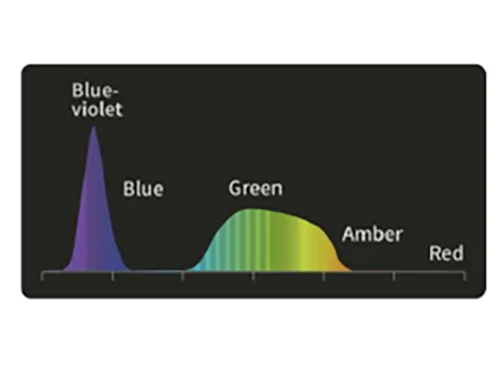

DSI: Узкоспектральная двухцветная визуализацияа

Свет фиолетового и зеленого спектров наиболее эффективно поглощается гемоглобином, что снижает отражение и рассеяние и позволяет четко визуализировать поверхностные сосуды слизистой оболочки. Увеличивает контраст между кровеносными сосудами и окружающей тканью.

Белый свет

DSI